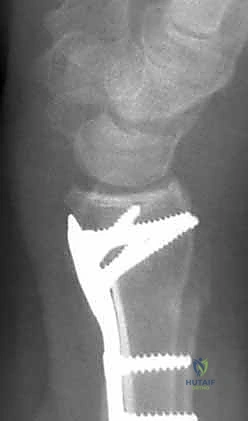

4. وضع الصفيحة والتثبيت المؤقت

يتم اختيار صفيحة تيتانيوم مصممة تشريحياً لتلائم انحناء الكعبرة. توضع الصفيحة على العظم وتُثبت مؤقتاً بأسلاك معدنية دقيقة (K-wires).

5. حفر العظم ووضع المسامير

يتم حفر ثقوب في العظم عبر فتحات الصفيحة، ثم تُقاس المسافات بدقة لإدخال مسامير القفل (Locking Screws) في الجزء البعيد (قرب المفصل) ومسامير قشرية في الجزء القريب (في ساق العظم).

6. الفحص النهائي والإغلاق

يتم إجراء فحص أخير بالأشعة للتأكد من المحاذاة المثالية للكسر وأطوال المسامير (لضمان عدم بروزها واحتكاكها بالأوتار الخلفية). بعد ذلك، يتم خياطة الأنسجة والجلد بخيوط تجميلية ووضع ضمادة معقمة.